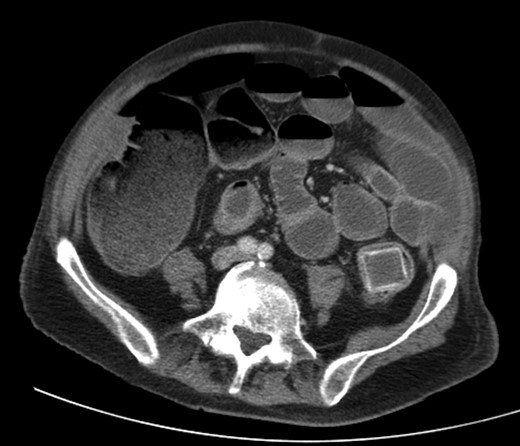

A 92-year male, with no significant co-morbidities apart from peptic ulcers, was admitted with 6 days of obstination. On examination he was dehydrated, with a hugely distended abdomen but no signs of peritonitis. Blood showed features of dehydration and plain abdominal X-ray demonstrated both small and large bowel dilatation, but no obvious causal pathology. A contrast-enhanced computed tomography scan revealed a 2.5-cm partially calcified gallstone impacted at the descending colon-sigmoid junction (Fig. 1). There was no stricture or diverticular disease distal to the stone. A cholecysto-colic fistula could be seen (Fig. 2), with a further smaller gallstone in the caecum (Fig. 3). The offending gallstone could be seen incidentally in the gallbladder on imaging 3 years previously (Fig. 4).

Large gallstone impacted in the descending colon-sigmoid junction, causing large bowel obstruction proximally.